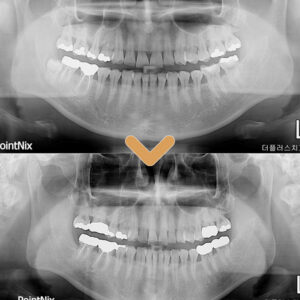

수암동치과 임플란트 오래동안 튼튼하게 사용할 수 있는

치아는 우리 신체에서 다양한 기능을 수행하고 있는 중요한 기관 중 하나입니다.   앞니는 주로 시각적으로 노출되어 있어 미소와 표정의 아름다움을 담당하며, 어금니는 강력한 저작 기능을 통해 음식을 부수고 소화를 돕는 중요한 역할을 합니다.   이처럼 다양한 기능을 수행함에 따라, 더보기…